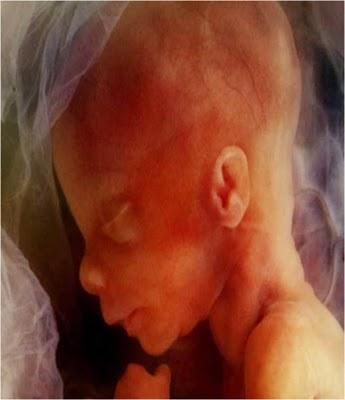

ÉL COMPLETA 24 SEMANAS.DE SUS ÓRGANOS, SOLAMENTE LOS PULMONESNO ESTÁN COMPLETAMENTE FORMADOS.

EN ESTA ETAPA YA MUEVE SUS BRAZOS Y SUS PIERNAS, GUIÑA LOS OJOS, CHUPA SUS DEDOS E, INCLUSIVE,TIENE SUS PRIMEROS ACCESOS DE HIPO.

ESTÁ CADA VEZ MÁS CONSCIENTEDE EL ESPACIO QUE LO RODEA.

COMO TODOS LOS FETOS, PASA LA MAYOR PARTE DEL TIEMPODORMIDO Y, CUANDO DUERME, NADA CONSIGUE DESPERTARLO.LLEGA INCLUSO A SOÑAR.